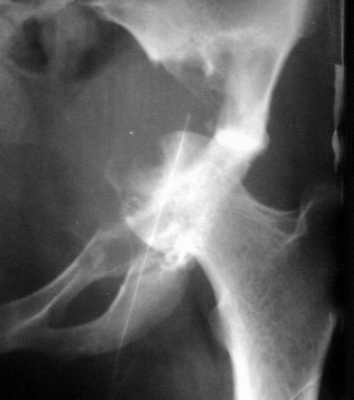

Остеобластокластома вертлужной впадины

Женщина 22 лет поступила с протрузией вертлужной впадины.Рентгенограммы (1, 2) с интервалом в 1 год. В онкодиспансере сделали биопсию - ОБК без малигнизации. Какой объем операции здесь следует предпринять? Есть ли какие-то шансы на первичное эндопротезирование? Где такие операции делают? В том числе в Европе. Заранее спасибо.

The xray appearance is consistent with a bengin aggessive or malignant lesion involving both the acetablum and the femoral epiphysis (there appears to be erosions of the femoral head). The differential diagnosis would include non-tumor conditions such as Brown's tumor (a serum calcium should be measured), benign aggressive lesions such as GCT, ABC and chondroblastoma, and malignant lesions such as telangiectatic osteosarcoma and MFH of bone.

However, the extent of the tumor in the pelvis and lack of a cortical rim leading to a large uncontained defect would be too much bone loss for any type of acetabular reconstruction.

A wide resection with reconstruction with a saddle modular prosthesis would be an option depending on the status of the remainder of the ilium.

looking to the X-rays and CT scan it appears this young lady has an aggressive bone leasion.

The X-ray and CT scan appearance is likely as the chondrosarcoma what is seldom but common

finding in the replacement surgery of the hip. Having precise histological, CT and MRI data should be planed the amount of surgery after detailed discussion with patient. There is no any possibility to perform primary replacement. If there is the chondrosarcoma hemipelvectomy would be the most live saving procedure. If there is an aggressive giant cell tumor or other findings about allografting, reconstructive surgery with custom made implant or saddle modular prostheses (W.Link) could be discussed. In other wards there are so many different thinks what should be discussed with patient